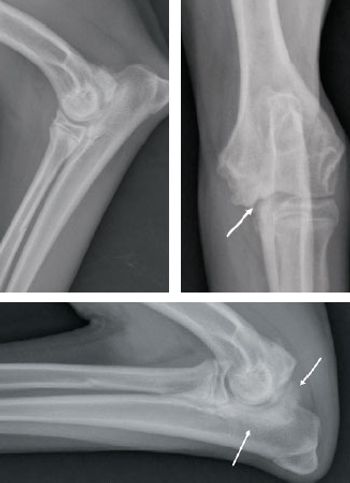

Find out which conditions are most likely and get general guidance on their diagnosis and treatment. (Part 1 of a 2-part series)